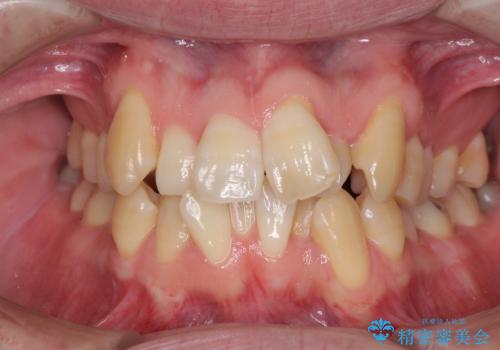

[インビザライン] 前歯のガタつき・すれ違い マウスピース矯正治療

![[インビザライン] 前歯のガタつき・すれ違い マウスピース矯正治療の症例 治療前](https://seimitsushinbi.jp/wp/wp-content/uploads/2021/08/0b21121c07cfd741f7e6e7110f2c1705-500x350.jpg?v=1629705726)